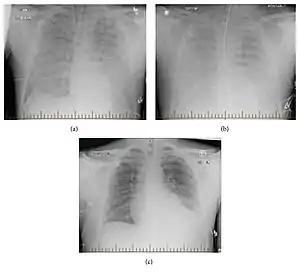

| Progression of hantavirus pulmonary syndrome | |

In the following 5–7 day cardiopulmonary phase, the patient's condition rapidly deteriorates into acute respiratory failure, characterized by the sudden onset of shortness of breath with rapidly evolving pulmonary edema, as well as cardiac failure, with hypotension, tachycardia and shock.[1] In this phase, patients may develop acute respiratory distress syndrome. It is often fatal despite mechanical ventilation and intervention with diuretics.